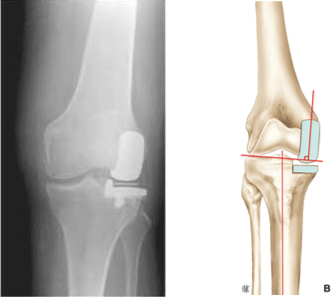

Uni-compartmental prosthesis

This is a surgery in which only the damaged compartment of the knee is replaced with an implant.

The knee can be divided into three compartments: femoro-patellar, medial femoro-tibial, and lateral femoro-tibial. A unicompartmental knee replacement is an option if osteoarthritis affects only one compartment of your knee.